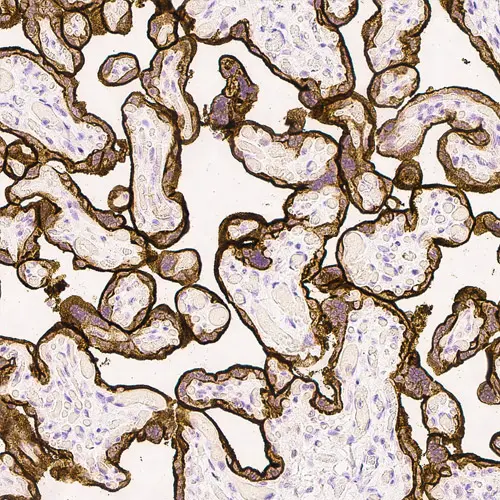

Human placenta: immunohistochemical staining for Epidermal Growth Factor Receptor. High expression of EGFR localized in the trophoblastic layer of the placental villi. Epidermal Growth Factor Receptor: clone EGFR.113

Il clone EGFR.25 è diretto contro il dominio citoplasmatico della molecola del EGFR, mentre il clone EGFR.113 è diretto contro il suo dominio extracellulare.